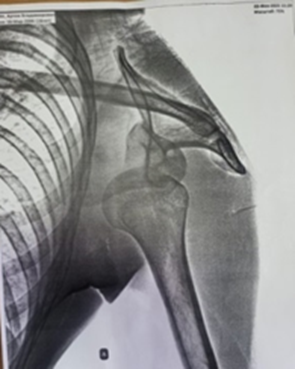

После клинического, рентгенологического обследования был выставлен диагноз: Хроническая рецидивирующая передняя нестабильность левого плечевого сустава. Привычный вывих левого плеча (рис. 1). Дежурным травматологом было произведено закрытое вправление вывиха под внутривенным наркозом. Иммобилизация косыночной повязкой. На контрольной рентгенограмме вывих головки плечевой кости вправлен (рис. 2).

Рис. 1. Первичная рентгенограмма левого плечевого сустава после эпизода повторного вывиха плеча

Примечание: составлен авторами на основе рентгенологического исследования левого плечевого сустава